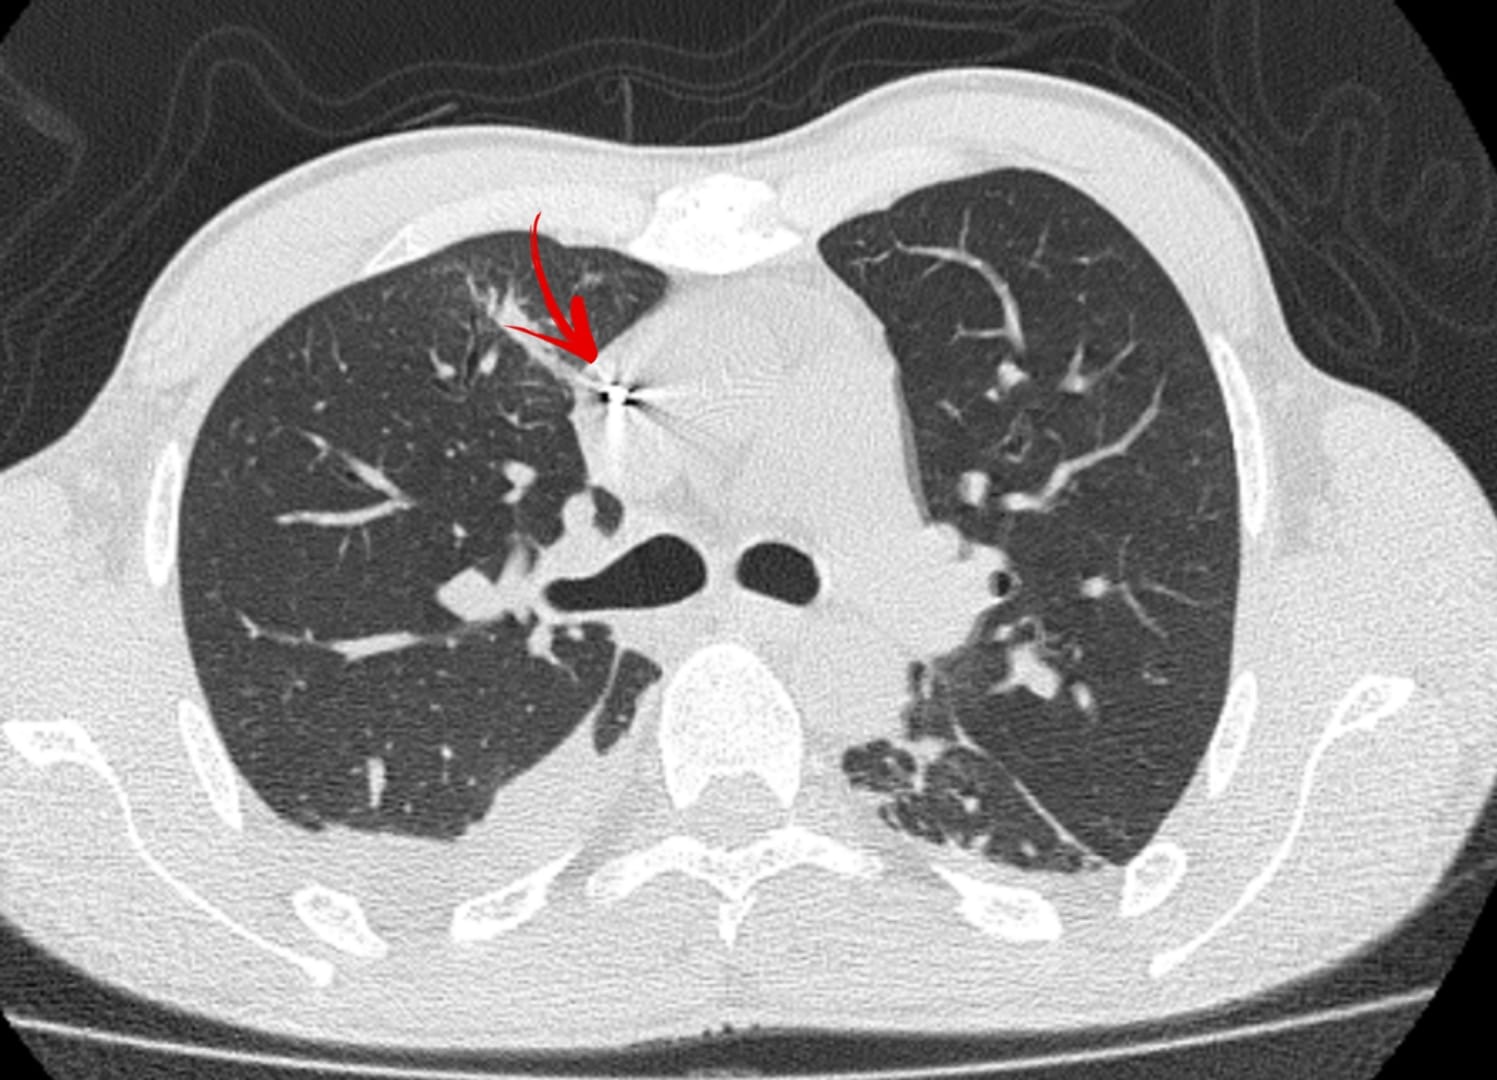

До Вінницької обласної лікарні імені Пирогова доставили пацієнта з проникаючою травмою правої половини грудної клітки, була пошкоджена права легеня та праві відділи серця.

Під час дообстеження лікарі виявили металевий уламок в серці, який міг щомиті викликати ускладнення. Аби врятувати життя пацієнта, необхідно було негайно видалити стороннє тіло.